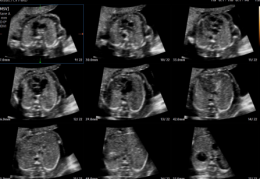

V7 OB

V7 OB – Ecógrafos para Obstetricia y Ginecología

El V7 OB optimiza la atención de la salud femenina, desde fertilidad hasta seguimiento del embarazo. Combina Crystal Architecture™ con Intelligent Assist™, permitiendo flujo de trabajo eficiente, imágenes de alta calidad y diagnósticos confiables.

Aplicaciones: Obstetricia, ginecología, fertilidad, salud materno-fetal.